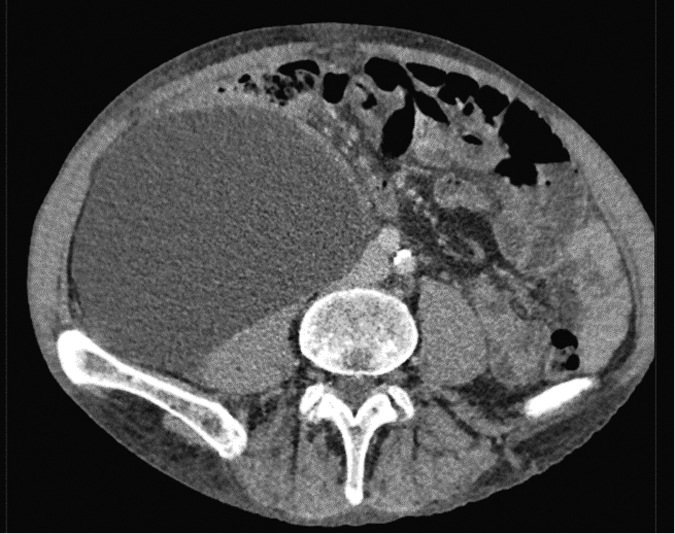

Retroperitoneal hematoma is a rare but serious complication. It has an incidence of 0.8%–0.44%. The occurrence of this pathology is associated primarily with suprainguinal puncture of the external iliac artery. The main danger consists in the delayed manifestation of symptoms, namely hypovolemia, pain in the ipsilateral hypogastrium, and deterioration in the general condition of the patient. Diagnosis is based on physical examination, ultrasound scan, and CT scan with contrast agent. Treatment includes an emergency revision with the imposition of a vascular suture, hematoma evacuation, and drainage in the retroperitoneal space. In some cases, interpolate implantation and blood transfusion are required. Rebleeding or lymphocele occurs in rare cases (Figure 4).